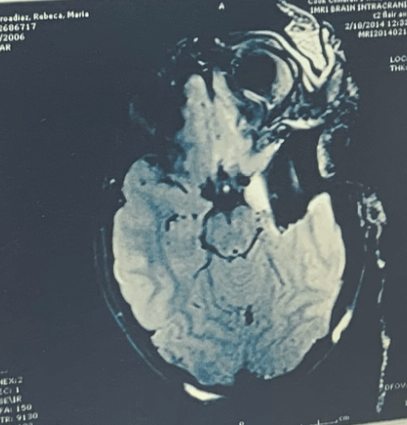

Rebeca sufría de epilepsia refractaria focal de origen estructural. Fue operada a los 7 años para remover 20% de su cerebro dañado.

Radiografías del cerebro de Rebeca antes y después de extirparle el lóbulo temporal izquierdo.

El Cerebro de Rebeca antes de su cirugía

Antes de la cirugía

El Cerebro de Rebeca después de extirparle el lóbulo temporal izquierdo

Después de la cirugía